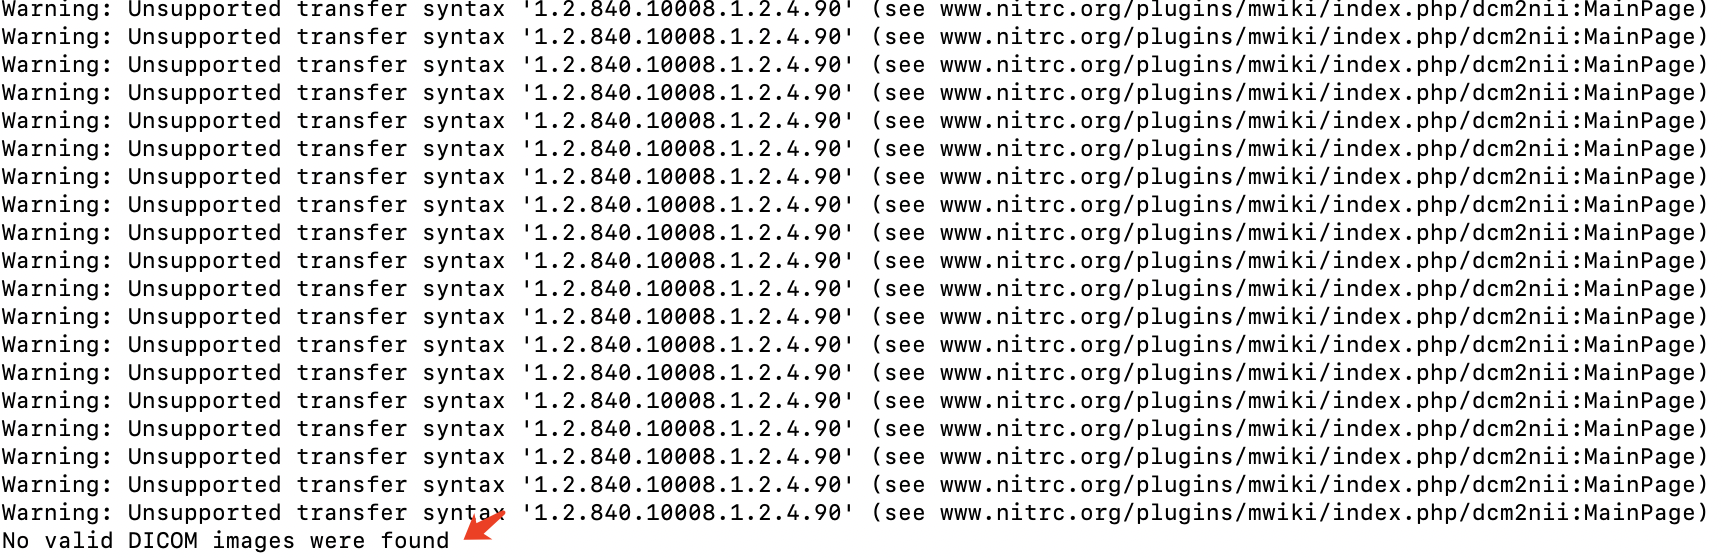

注意:我在 mac 中使用 MRIcroGL 转 Nii 时,会提示没有有效的DICOM文件,但是我换成 MRICron 就能成功。奇了怪了,搞不懂,遇到同样问题的话,你就使用 MRICron。

这两种方法安装最简单,但不一定有效。比如,我在 mac 上使用这两种方法安装后,转 nii 时,总会提示下图错误

但是在 linux 上这样安装是可用的。